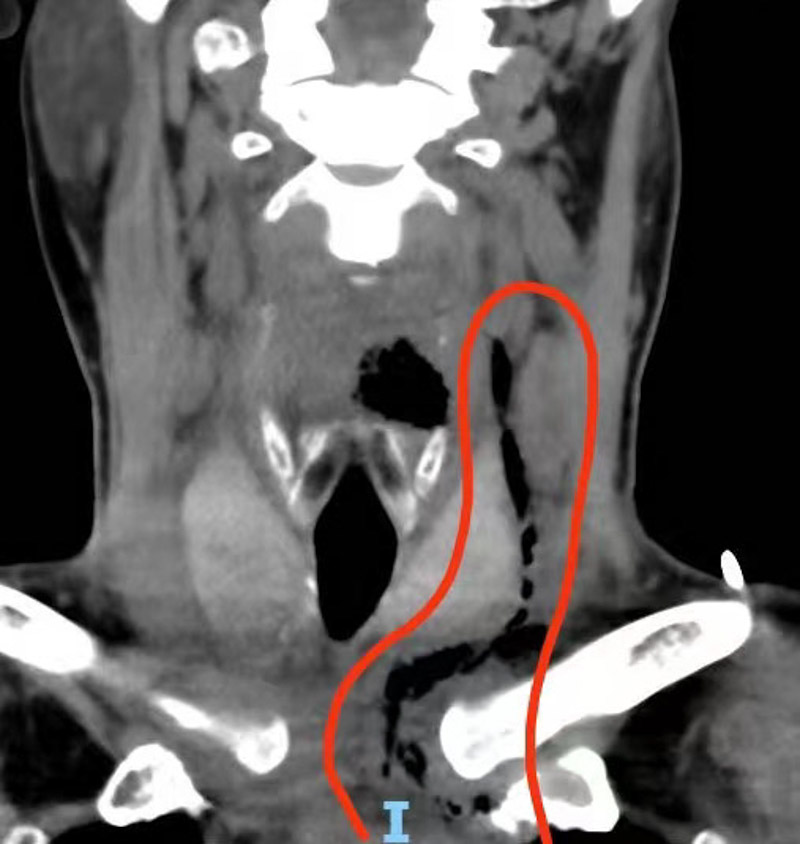

經檢查,發現患者頸部膿腫嚴重,感染已向縱隔發展同時合并心包感染, 生命危在旦夕,需要馬上手術治療。

據了解,縱隔膿腫是指由金黃色葡萄球菌侵入縱隔的組織和血管內,使組織壞死、液化,形成膿液積聚的急性結締組織化膿性感染,是一種病情發展迅速的感染性疾病。縱隔組織結構疏松,可迅速導致病菌周圍組織廣泛壞死,細菌或毒素通過縱隔豐富的淋巴管吸收很快產生菌血癥、毒血癥和敗血癥,甚至并發中毒性休克;還可引起心包炎、胸腔積膿、心肺功能衰竭和大血管腐蝕的致死性出血等不可救治的并發癥,死亡率高達70%,需經手術切開引流、抗炎等綜合治療。

術者仔細暴露縱隔結構,沿后縱隔間隙完整敞開膿腔并切除部分腔壁通暢引流,大量渾濁膿液從頸部下方溢出,反復沖洗后留置VSD引流管,經一個半小時,順利完成手術。